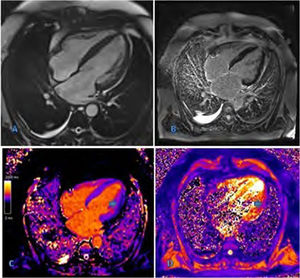

Iron heart: cardiomyopathy secondary to liver disease

Corazón de hierro: miocardiopatía secundaria a hepatopatía